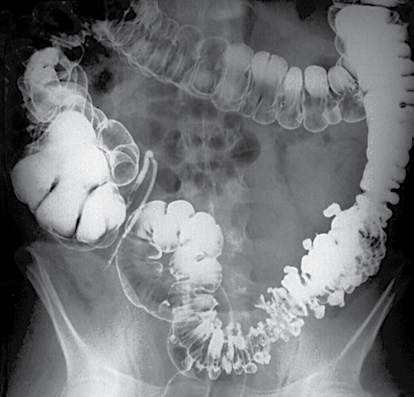

Analise o que segue.

A imagem é compatível com